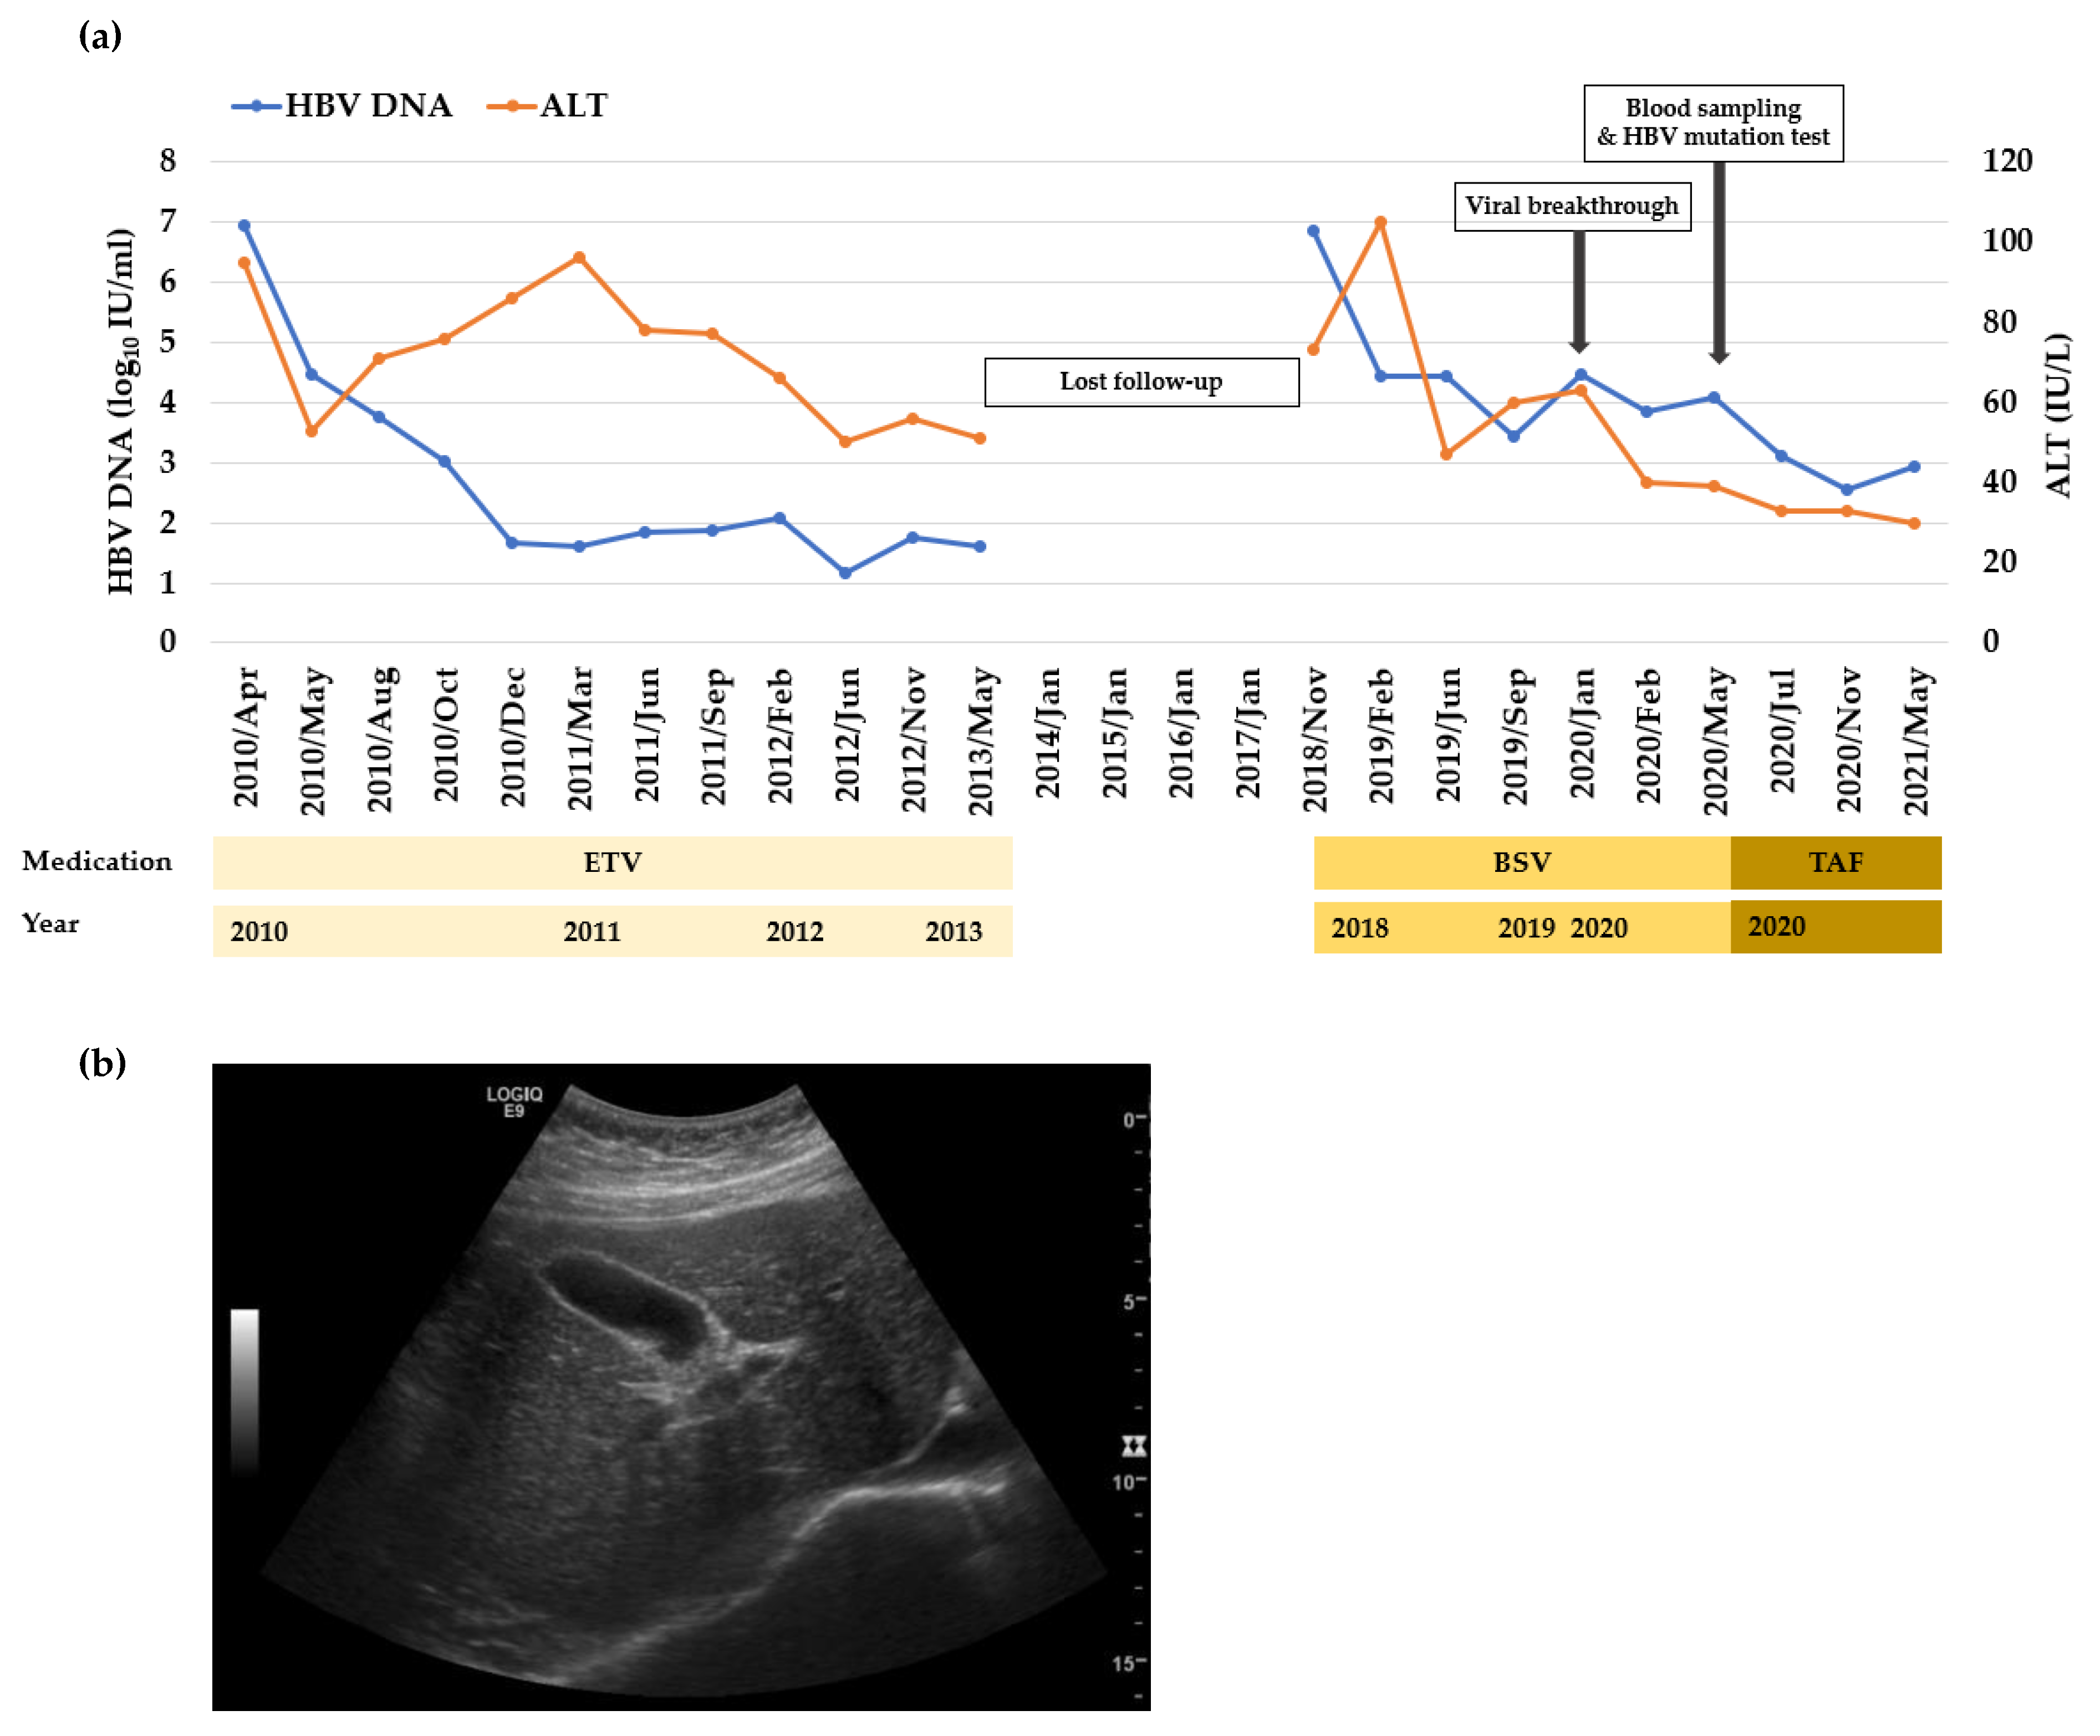

3.1. Mutation Profile of HBV RT Domain Isolated from a Patient Treated with BSV

| Variables | Values | Standard Levels |

|---|---|---|

| HBeAg | Positive | - |

| HBeAg antibody | Negative | - |

| HBV DNA (IU/mL) | 6,954,754.3 | - |

| bilirubin (mg/dL) | 0.81 | 0.2~1.2 |

| AST (IU/L) | 66 | 5~40 |

| ALT (IU/L) | 101 | 0~40 |

| Prothrombin time (s) | 11.6 | 9.5~13.5 |

| White blood cell (103/μL) | 5.46 | 4~10 |

| Serum albumin (mg/dL) | 4.5 | 3.3~5.2 |

| Hemoglobin (g/dL) | 13.6 | 12~16 |

| Platelet (103/μL) | 157 | 150~450 |